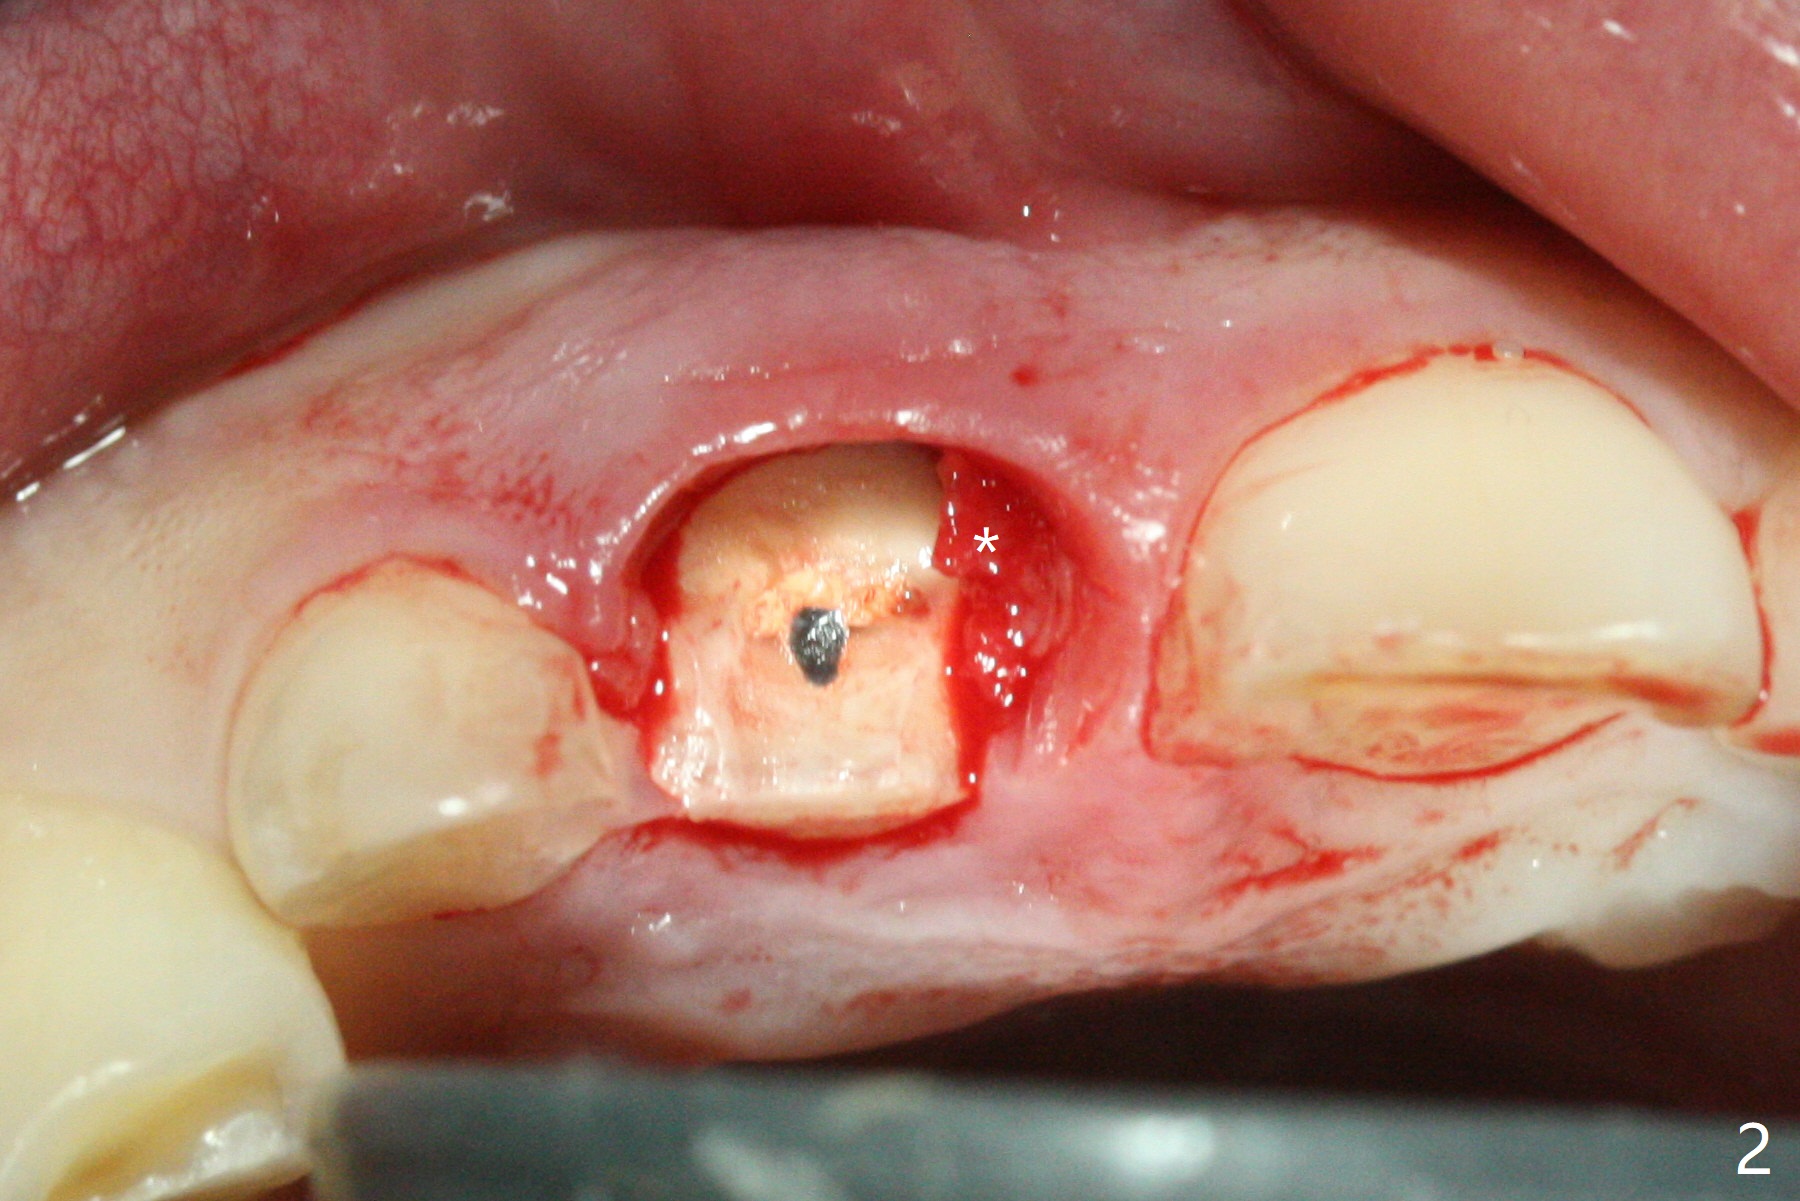

The buccal gingiva at #8 is erythematous (Fig.1: *), which is associated with the tooth fracture line (Fig.2 with granulation tissue: *). The buccal plate remains intact. Osteotomy is initiated in the palatal wall of the socket (Fig.3,4). The initial osteotomy depth is 16 mm (Fig.5); the trajectory is going to be adjusted as shown by arrows. The trajectory improves when a 3.8x15 mm dummy implant is placed (Fig.6). The definitive implant (3.8x16 mm) appears to be placed at an appropriate level (Fig.7). A 4.5x3 mm temporary abutment is inserted for an immediate provisional. As routine, Vera Graft is placed in the buccal gap. The buccal gingival erythema reduces without tenderness 1 week postop (Fig.8). Although the provisional is unstable, there is no bone loss 2 months 20 days postop (Fig.9). Because of the loose provisional (partial detachment from the underlying temporary abutment), impression is taken earlier (3 months postop, Fig.10,11). Due to the pointed abutment tip, the crown is redone 3 times. By the time of cementation (nearly 5 months postop), the socket appears to have healed (Fig.12).